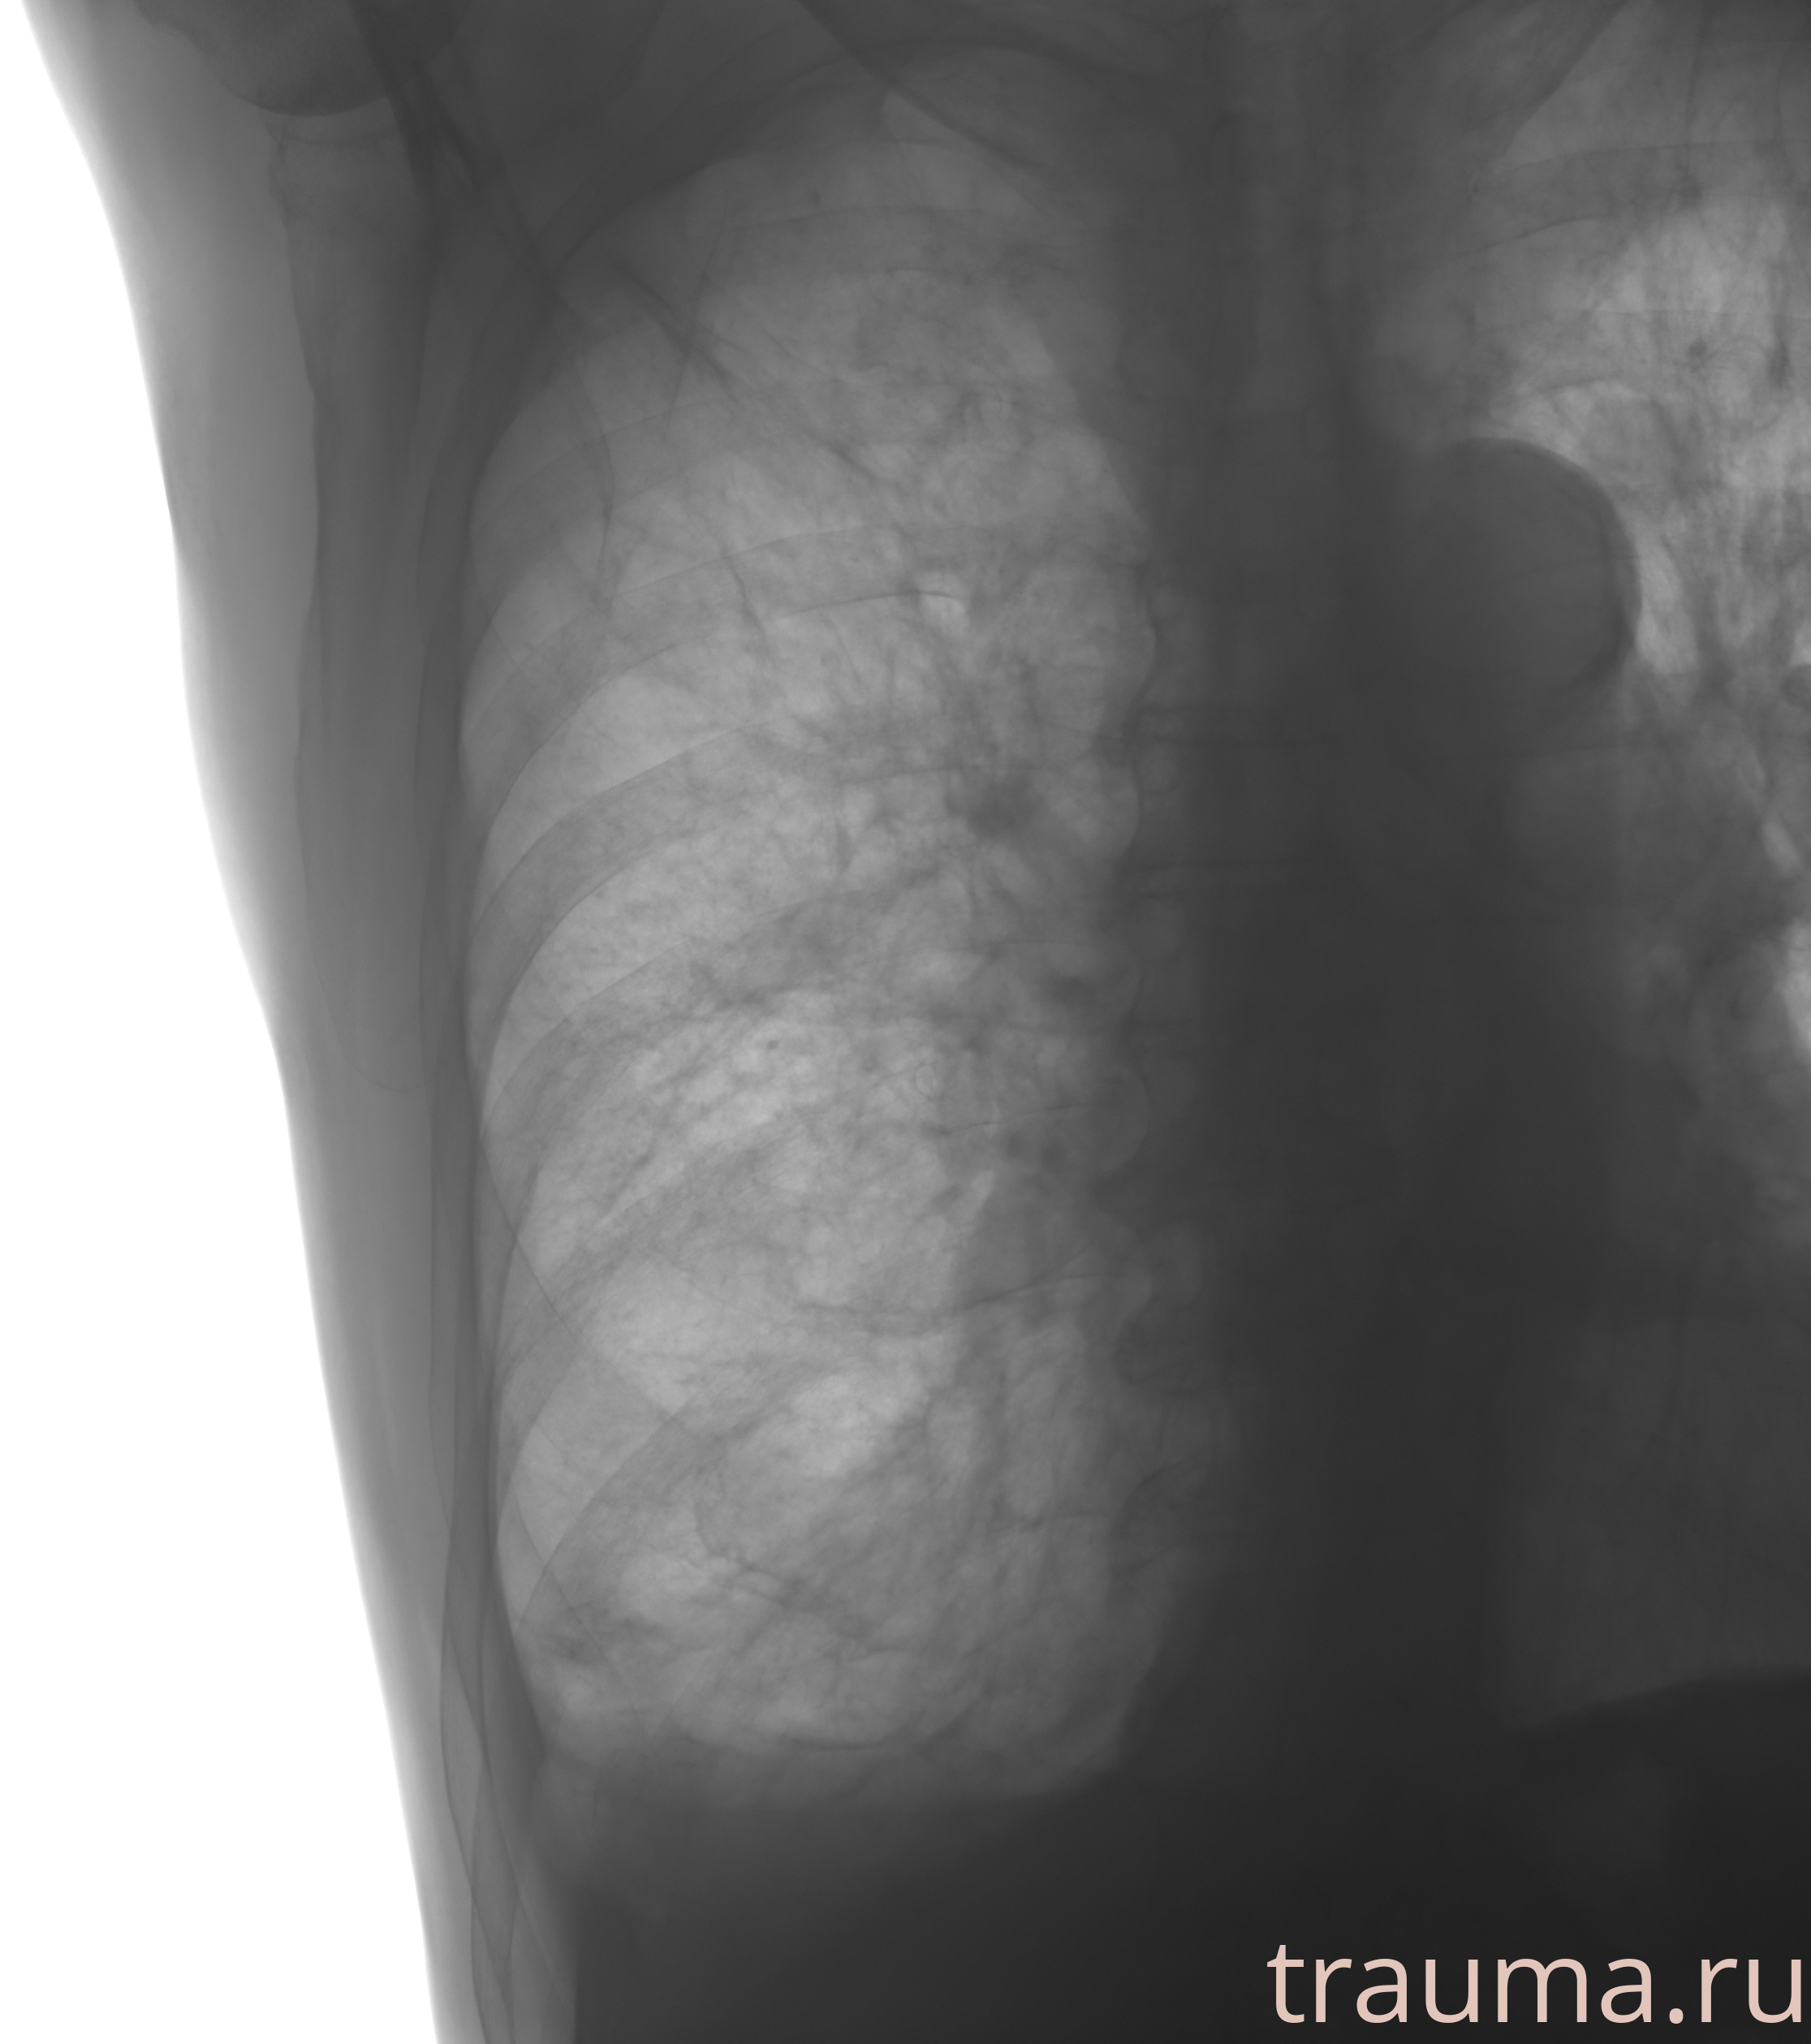

Рентген на дому: по вашему адресу приезжает врач-рентгенолог, травматолог-ортопед с мобильным рентгеновским аппаратом, проводит диагностику травмы или заболевания, делает необходимые рентгенограммы, дает рекомендации по дальнейшему лечению. Получить качественные снимки в домашних условиях возможно благодаря уникальной методике, разработанной МосРентген Центром для института  Склифосовского